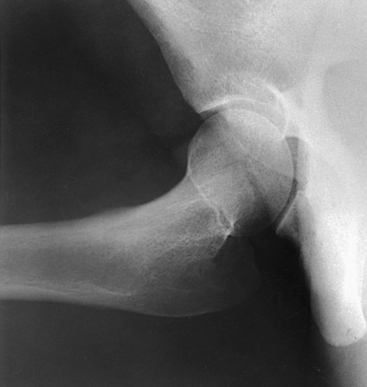

The Lauenstein and Hickey methods are used to show the hip joint and the relationship of the femoral head to the acetabulum. This position is similar to the previously described modified Cleaves method.

Structures shown: The resulting image shows a lateral projection of the hip including the acetabulum, proximal end of the femur, and relationship of the femoral head to the acetabulum (see Figs. 7-33 and 7-34).